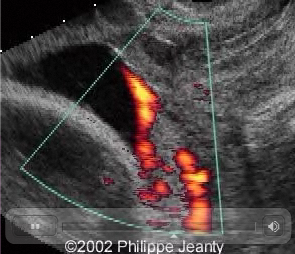

Source: www.thefetus.net

This is an artery with an interior velamentous insertion. Note on the greyscale there is no evidence of vasa praevia, but as the scan progresses to colour and the power doppler it is clear there is vasa praevia.

Again, there is no reason not to use colour doppler during these examinations. The diagnosis would have been missed otherwise.